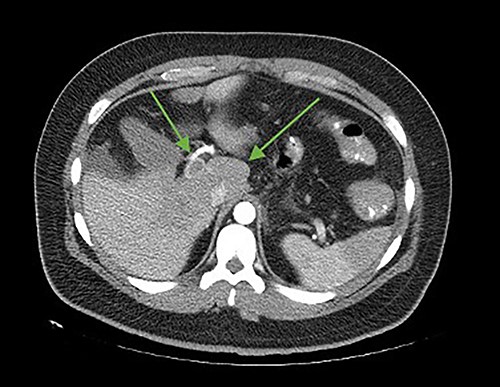

The patient was reoperated by laparoscopy, finding segmental thrombosis from 200 cm to 50 cm of the Treitz ligament, with edema and interloop free fluid without perforation (Figs 3 and 4). Lateral resection and entero–entero anastomosis were performed with manual stapler, subtracting 440 cm of intestine with adequate coloration. Later he was admitted to the Intensive Care Unit, treated with low molecular weight heparin at a full anticoagulation dose, maintaining an INR of 2 and a partial thromboplastin time of 80 s. He presented adequate evolution starting a liquid diet on the fourth postoperative day, new laboratories reported hemoglobin of 11 g/dl, 12 700 leukocytes/mm3, platelets 225 000/mcL, INR of 2. He was discharged on the fifth day with rivaroxaban treatment for 6 months.

Laparoscopic view of intestinal thrombosis and free fluid in the cavity.